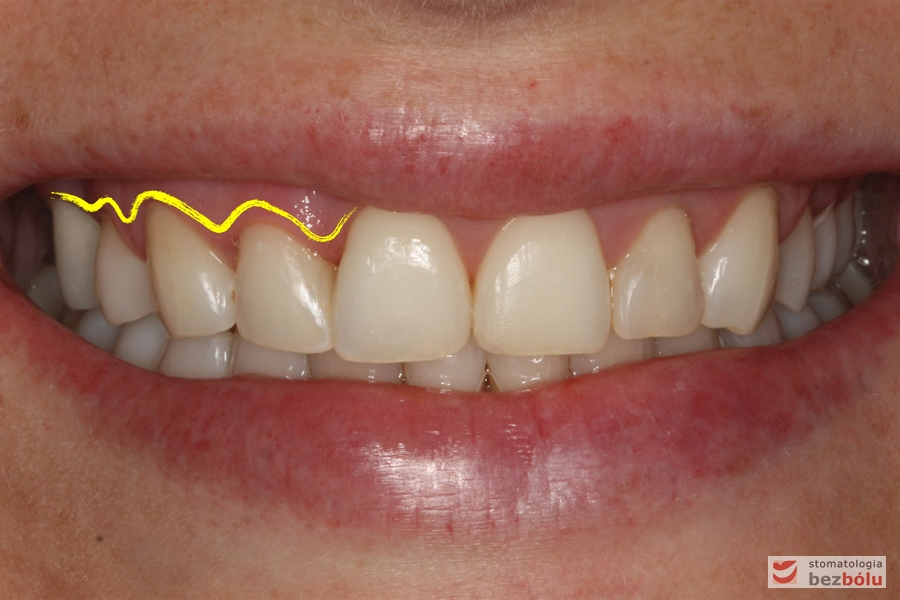

Młoda i urodziwa pacjentka (28 lat) zgłosiła się w celu korekcji wystającej i zrotowanej „jedynki” prawej górnej. Przeprowadzona diagnostyka wykazała: nieregularną linię dziąsła, proporcje zębów ~85%,spłaszczony łuk górny po stronie prawej z powodu zgryzu krzyżowego, ząb 11 poza łukiem w mezjorotacji, zaburzone proporcje siekaczy bocznych w stosunku do centralnych, starcie patologiczne na kle górnym po stronie prawej, rozbieżne osie długie w obrębie siekaczy i nieregularną linię dziąsła w obrębie stłoczonych siekaczy.

Diagnostyka – nieregularna linia dziąsła, proporcje zębów ~85%

Ocena brzegów siecznych w uśmiechu względem wargi dolnej